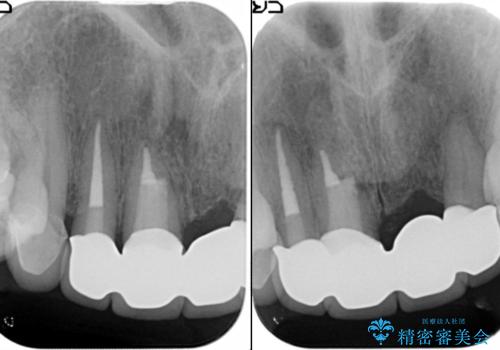

[ セラミック治療 ] 歯ぐきの際の黒ずみを改善したい

- 歯ぐきとセラミックの間の黒ずみが目立つので、きれいに治してほしい。と希望され来院されました。

歯ぐきの位置が変化しクラウン下の歯が見えるようになってしまったことで、審美障害が生じている状態です。

クラウンマージンの再設定を行うことで、黒ずんだ部分を再度覆い、審美障害を改善します。